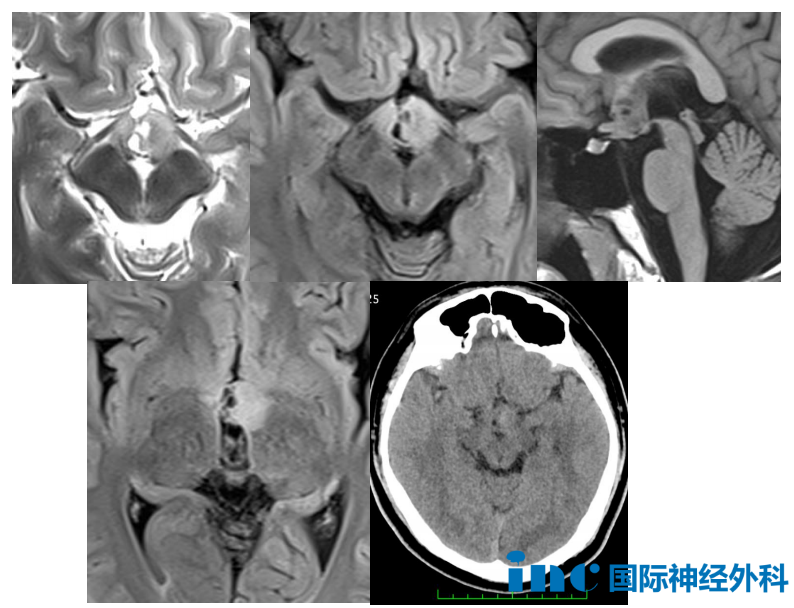

15岁男孩--视神经胶质瘤

“为什么我的孩子不能全切……”阿豪的母亲一直询问巴教授。15岁的阿豪核磁检查提示左侧下丘脑及三脑室无强化结节、左侧丘脑前部、鞍上结节,考虑错构瘤或视神经胶质瘤。对于未来的治疗策略,一部分医生建议患者目前无任何症状,可以继续观察,一部分认为孩子应该接受手术,但是由于肿瘤位置在丘脑,手术风险很大,不可能做到全切。

巴教授评估回复

手术目标不是根治性的切除,因为这样会导致严重的下丘脑功能失调。但是手术不仅仅是活检术,这取决于手术当中的情况。因此,只有在手术中,当我能亲眼看到病变并根据术中所见评估,我才能够确认病变的切除范围。